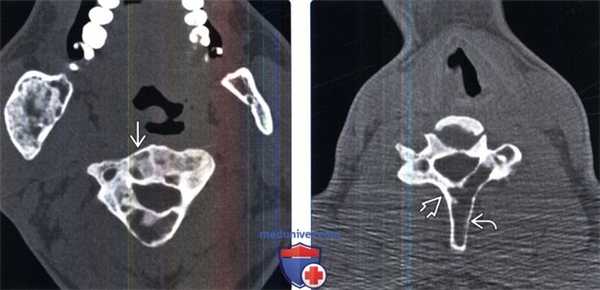

(Слева) Аксиальный КТ-срез: изменения различной плотности в пределах одного позвонка в сочетании с практически полным замещением костного мозга. Подобные изменения типичны для ФД и не должны служить основанием для подозрений на злокачественный характер процесса.

(Справа) Аксиальный КТ-срез: литический очаг ФД в задних элементах позвонка. Наличие узкой переходной зоны (иногда склеротической) помогает отличить ФД от более агрессивных поражений. Тела позвонков обычно поражаются в меньшей степени, чем задние элементы.